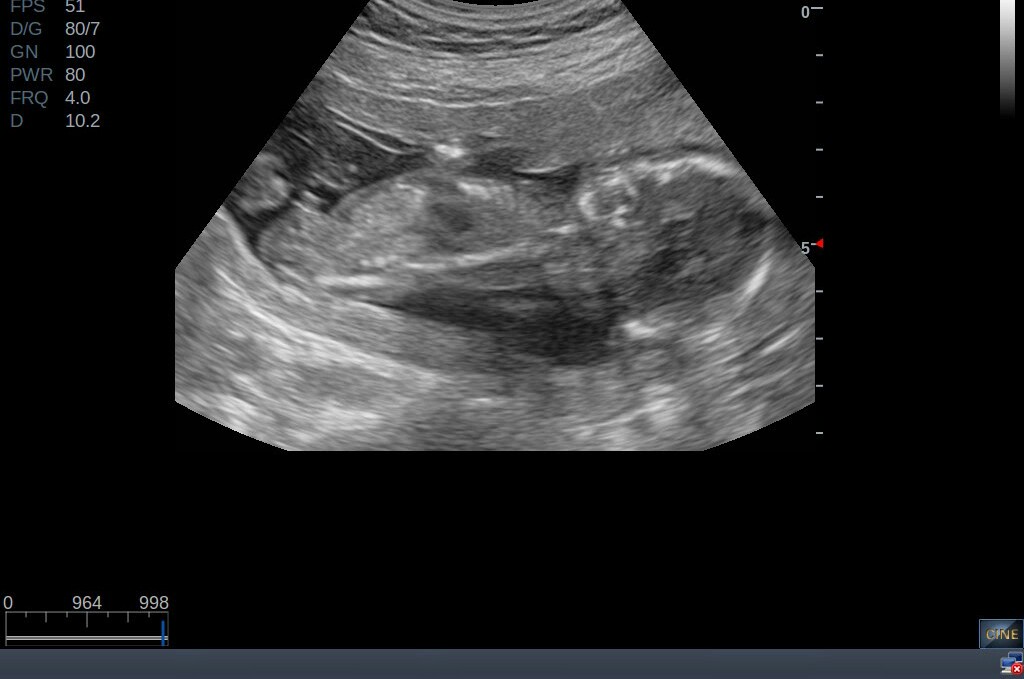

I don't really know much about nubs but as I'm looking thru some u/s pics I see something sticking out here. Is that a boy nub?Attachment 35227

This must be the cord then right?

Bottom one is definitely cord. The top one is tricky. It looks like a boy nub, but the angle of the baby makes me think that too is cord showing through.

I can see a girlie nub on the top one. I'm thinking this is a girl.

I did! I was split with those 50/50. Seeing these now make me wonder if the cord was in a precarious position making it appear to look boyish. I'm hoping I'm right!

I would mentally prepare to hear boy, but I'm not completely convinced [emoji6]!

See how the back is arched though DJ?? I am not convinced that is not a baby with an arched back and cord making it look like a stacked nub.

I would never, ever, ever in a million years want to mislead or give you false hope. But I am just really not sure on these and thus I do not want you to be in either false hope but also not in false despair. still 50-50 from me.